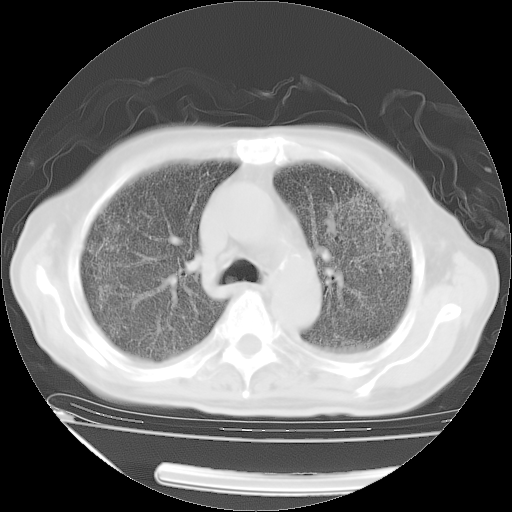

经过24天治疗,岳父的病情基本稳定。生活基本可以自理,可以下床活动。呼吸困难早已消失。体温基本正常。

主要治疗甲强龙80mg×14天,60mg×10天;同时抗结核(异烟肼+利福平+乙胺丁醇)。环磷酰胺0.1 tid 10天。

特别感谢胡教授、高管、桃子版主给出关键的治疗建议。桃版把所有肺部影像和全部临床资料请所在医院呼吸科、感染病科、结核科、临床免疫科专家会诊。临床免疫科专家制定了完整的治疗方案。